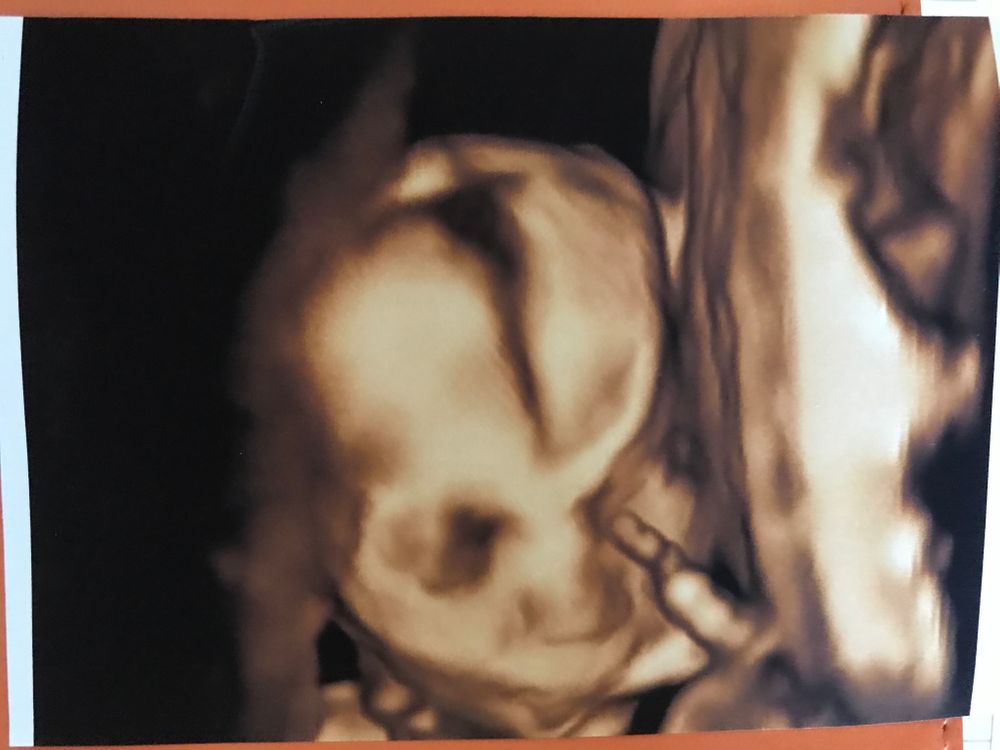

2 скрининг, завтра уже 20 недель🥳

Всё о нашей беременностиМалышка развивается в соотвествии со сроком, все в норме💓💓💓

очень переживала за количество вод, живот не большой, боялась, вдруг ей там тесно. Но тоже все в норме и рыбке нашей там хорошо🥰 Крошечка совсем 311г